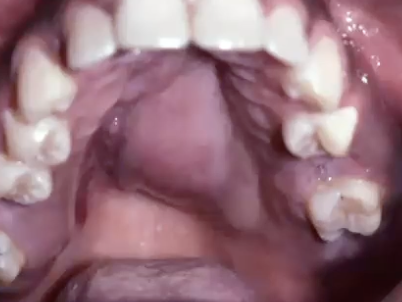

Concerning locations for salivary neoplasm

knowt flashcard image